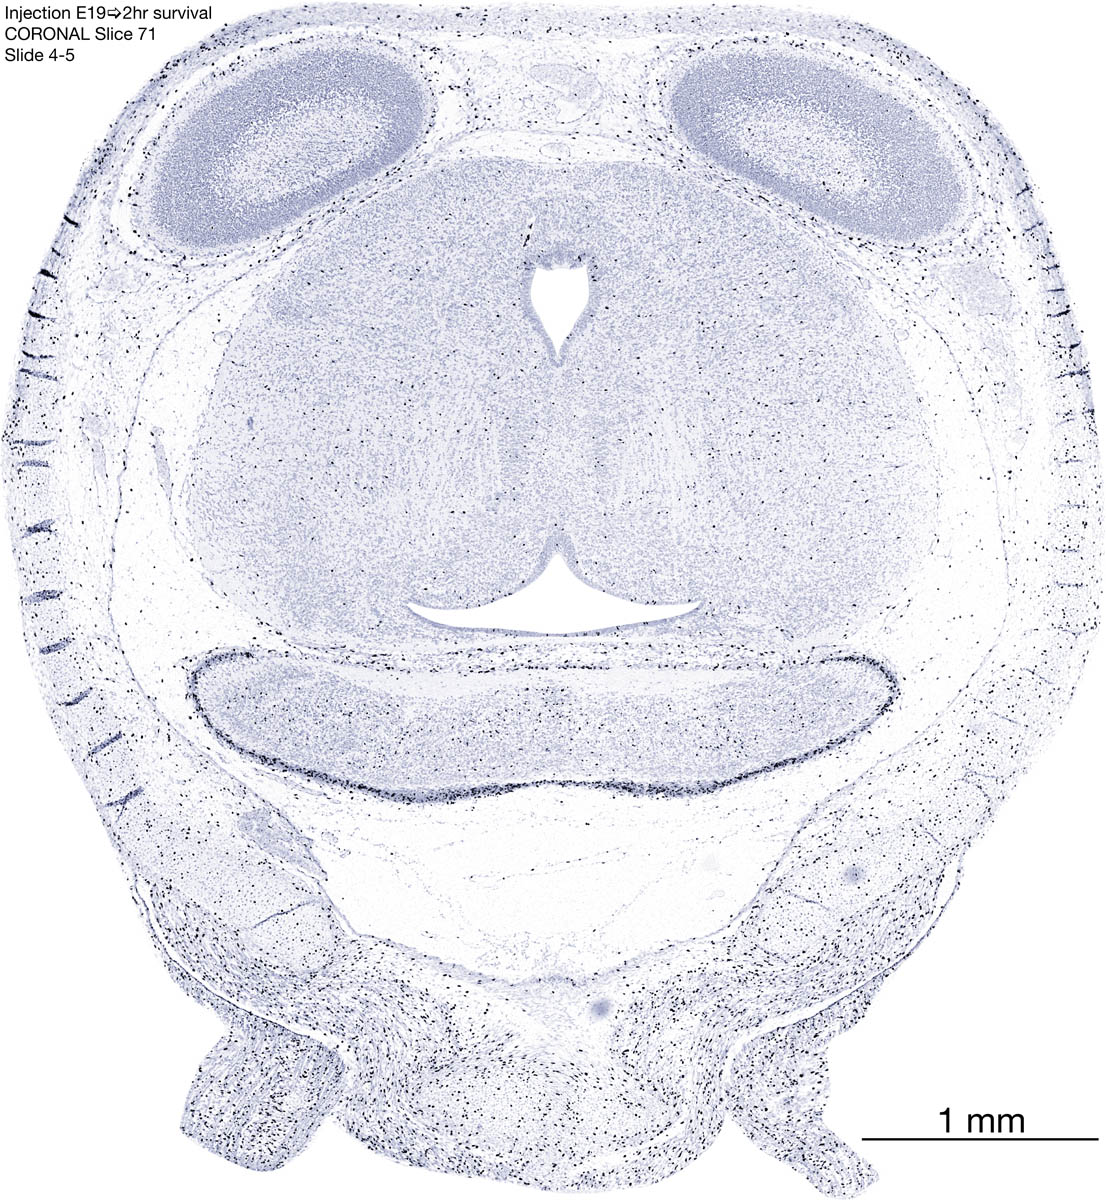

E19 2hr Survival Archived Images-Coronal The following images are from a paraffin-embedded coronally-sectioned head of an E19 rat embryo exposed to tritiated thymidine 2 hours before death. Download: Large | High Res Download: Large | High Res Download: Large | High Res Download: Large | High Res Download: Large | High Res Download: Large | High Res Download: Large | High Res Download: Large | High Res Download: Large | High Res Download: Large | High Res Download: Large | High Res Download: Large | High Res Download: Large | High Res Download: Large | High Res Download: Large | High Res Download: Large | High Res Download: Large | High Res Download: Large | High Res Download: Large | High Res Download: Large | High Res Download: Large | High Res Download: Large | High Res Download: Large | High Res Download: Large | High Res Download: Large | High Res Download: Large | High Res Download: Large | High Res Download: Large | High Res Download: Large | High Res Download: Large | High Res Download: Large | High Res Download: Large | High Res Download: Large | High Res Download: Large | High Res Download: Large | High Res Download: Large | High Res Download: Large | High Res Download: Large | High Res Download: Large | High Res Download: Large | High Res Download: Large | High Res Download: Large | High Res Download: Large | High Res Download: Large | High Res Download: Large | High Res Download: Large | High Res Download: Large | High Res Download: Large | High Res Download: Large | High Res Download: Large | High Res Download: Large | High Res Download: Large | High Res Download: Large | High Res Download: Large | High Res Download: Large | High Res Download: Large | High Res Download: Large | High Res Download: Large | High Res Download: Large | High Res Download: Large | High Res Download: Large | High Res Download: Large | High Res Download: Large | High Res Download: Large | High Res Download: Large | High Res Download: Large | High Res Download: Large | High Res Download: Large | High Res Download: Large | High Res Download: Large | High Res Download: Large | High Res Download: Large | High Res Download: Large | High Res Download: Large | High Res Download: Large | High Res Download: Large | High Res Download: Large | High Res Download: Large | High Res Download: Large | High Res Download: Large | High Res Download: Large | High Res Download: Large | High Res Download: Large | High Res Download: Large | High Res Download: Large | High Res Download: Large | High Res Download: Large | High Res Download: Large | High Res Download: Large | High Res Download: Large | High Res